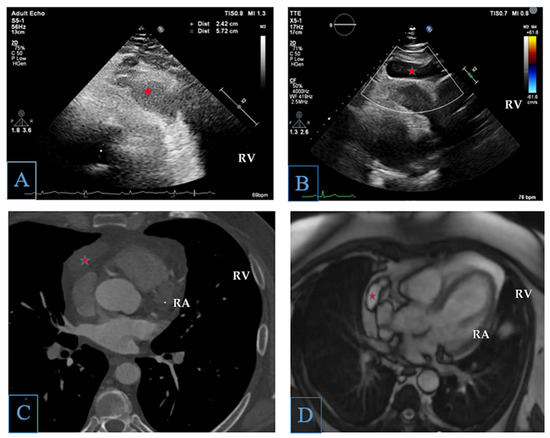

We report the case of a 53-year-old male patient who presented to the cardiology department with presyncope and atypical chest pain. The transthoracic echocardiography revealed a homogeneous hypoechoic mass measuring 2.5 × 5.7 cm at the level of the anterolateral wall of the [...] Read more.

We report the case of a 53-year-old male patient who presented to the cardiology department with presyncope and atypical chest pain. The transthoracic echocardiography revealed a homogeneous hypoechoic mass measuring 2.5 × 5.7 cm at the level of the anterolateral wall of the right ventricle. In order to further characterize the identified right-ventricle-adjacent mass, we performed a cardiac computed tomography, which confirmed the presence of a homogeneous hypodense mass with a single wall, without septation. Cardiac magnetic resonance imaging demonstrated a serous fluid mass capping the right atrium, right atrial appendage, and coronary sinus, without evidence of myocardial invasion. The multimodality imaging performed clarified the diagnosis of an uncomplicated pericardial cyst. The patient was managed conservatively with every 6 months echocardiographic evaluation. At a 2-year follow-up, he presented no recurrent symptoms, and the pericardial cyst maintained the same characteristics. The cornerstone of this case report was relying on multimodality imaging in order to characterize the adjacent cardiac mass and to arrive at the diagnosis of an uncomplicated pericardial cyst, which established the prognosis and management of the patient. Full article